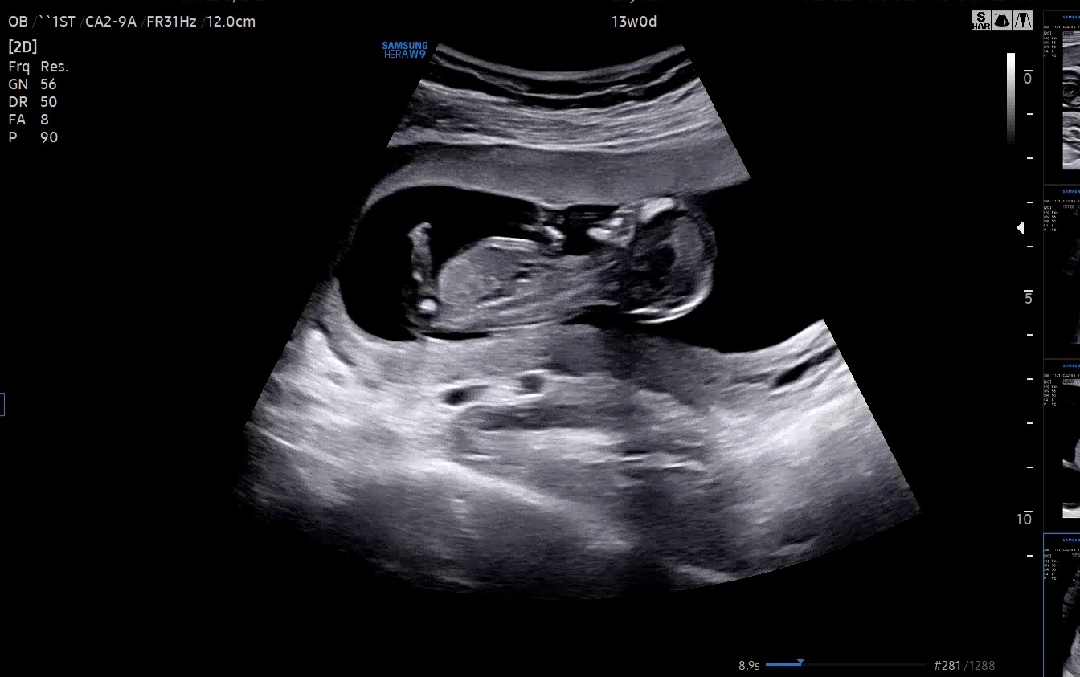

13주차 각도법 봐주세용